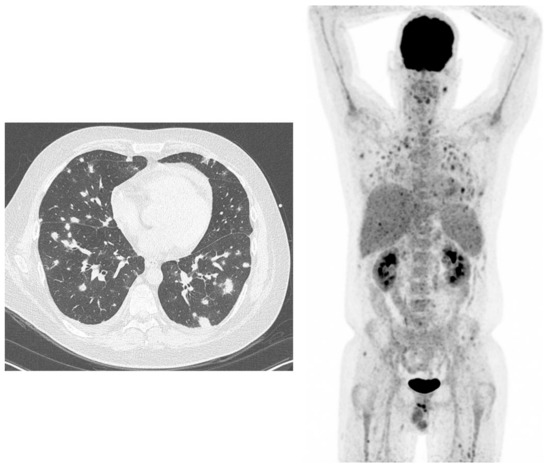

- Ankrah, O.A.; Span, L.F.R.; Klein, H.C.; de Jong, P.A.; Dierckx, R.A.J.O.; Kwee, T.C.; Sathekge, M.M.; Glaudemans, A.W.J.M. Role of FDG PET/CT in monitoring treatment response in patients with invasive fungal infections. Eur. J. Nucl. Med. Mol. Imaging 2019, 46, 174–183. [Google Scholar] [CrossRef]